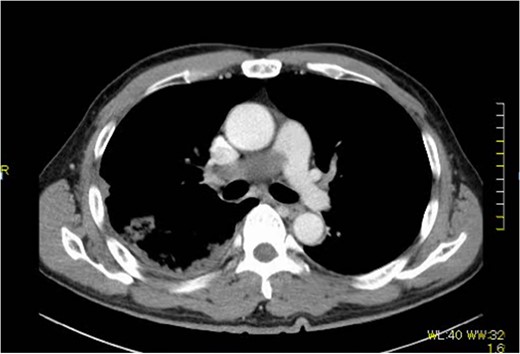

A 60-year-old man presenting with acute onset dyspnea and chest pain was referred to our institution. He had no past medical history. Physical examination was essentially normal except for weak respiratory sounds on the right side. Oxygen saturation was 88%. D-dimer was 1.43 mg/l. The electrocardiogram showed no ST changes. Chest radiography showed an abnormal shadow in the hilum of the right lung. Color Doppler ultrasound showed no deep vein thrombosis. Both the Wells Score and the Revised Geneva Score were 0. Transthoracic echocardiography showed normal left ventricular function (ejection fraction 62%), and no findings of pulmonary hypertension. Contrast-enhanced computed tomography (CT) showed a contrast defect lesion in the right and main pulmonary arteries, as well as a right pleural effusion (Fig. 1). He was initially diagnosed with PE according to the imaging findings and clinical presentation. Anticoagulant therapy (intravenous heparin infusion) was then started. Follow-up CT showed a larger defect lesion in the pulmonary artery, and the decision was then made to proceed with urgent pulmonary embolectomy because it was refractory to anticoagulant therapy. Cardiopulmonary bypass was established with aortic and bicaval cannulation. Deep hypothermic circulatory arrest was used every 10 minutes to obtain a bloodless field during pulmonary embolectomy. The right pulmonary artery was incised, and it was filled with a red, solid mass (Fig. 2). The mass was resected, and the pathological diagnosis during surgery was PAS. Because of the urgent situation, only endarterectomy, not pneumonectomy for radical resection of the tumor, was performed. On postoperative Day 7, CT showed residual lesions in the right pulmonary artery. The pathology report showed high-grade undifferentiated PAS (Fig. 3). The patient refused radical tumor resection by pneumonectomy, as well as postoperative radiation and chemotherapy. He died 5 months after the surgery.

Macro findings of the pulmonary artery show sarcoma and thrombus.